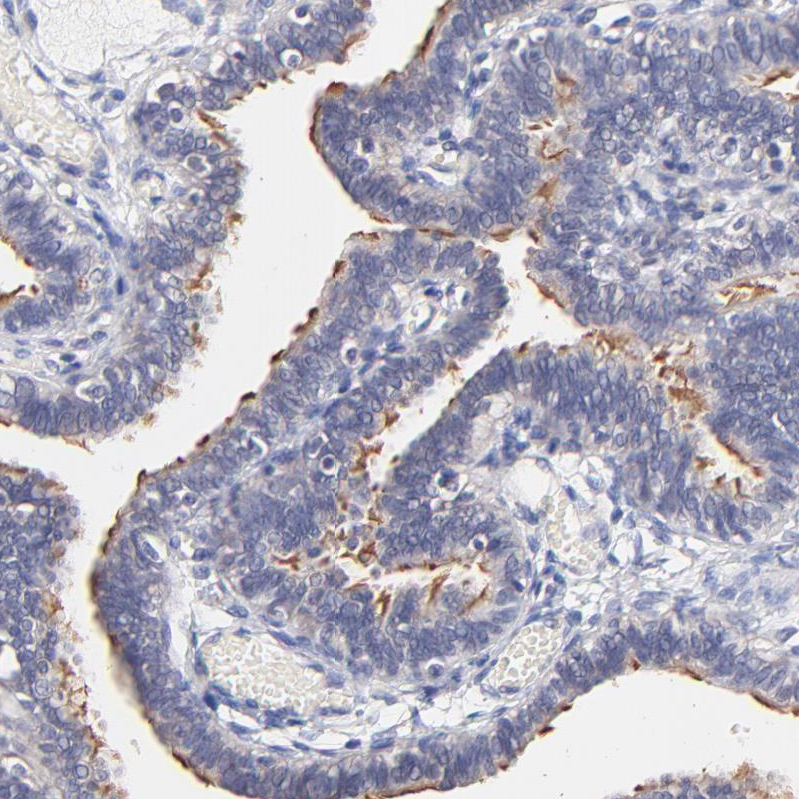

Immunohistochemical staining of human fallopian tube shows moderate to strong positivity in cilia in glandular cells.